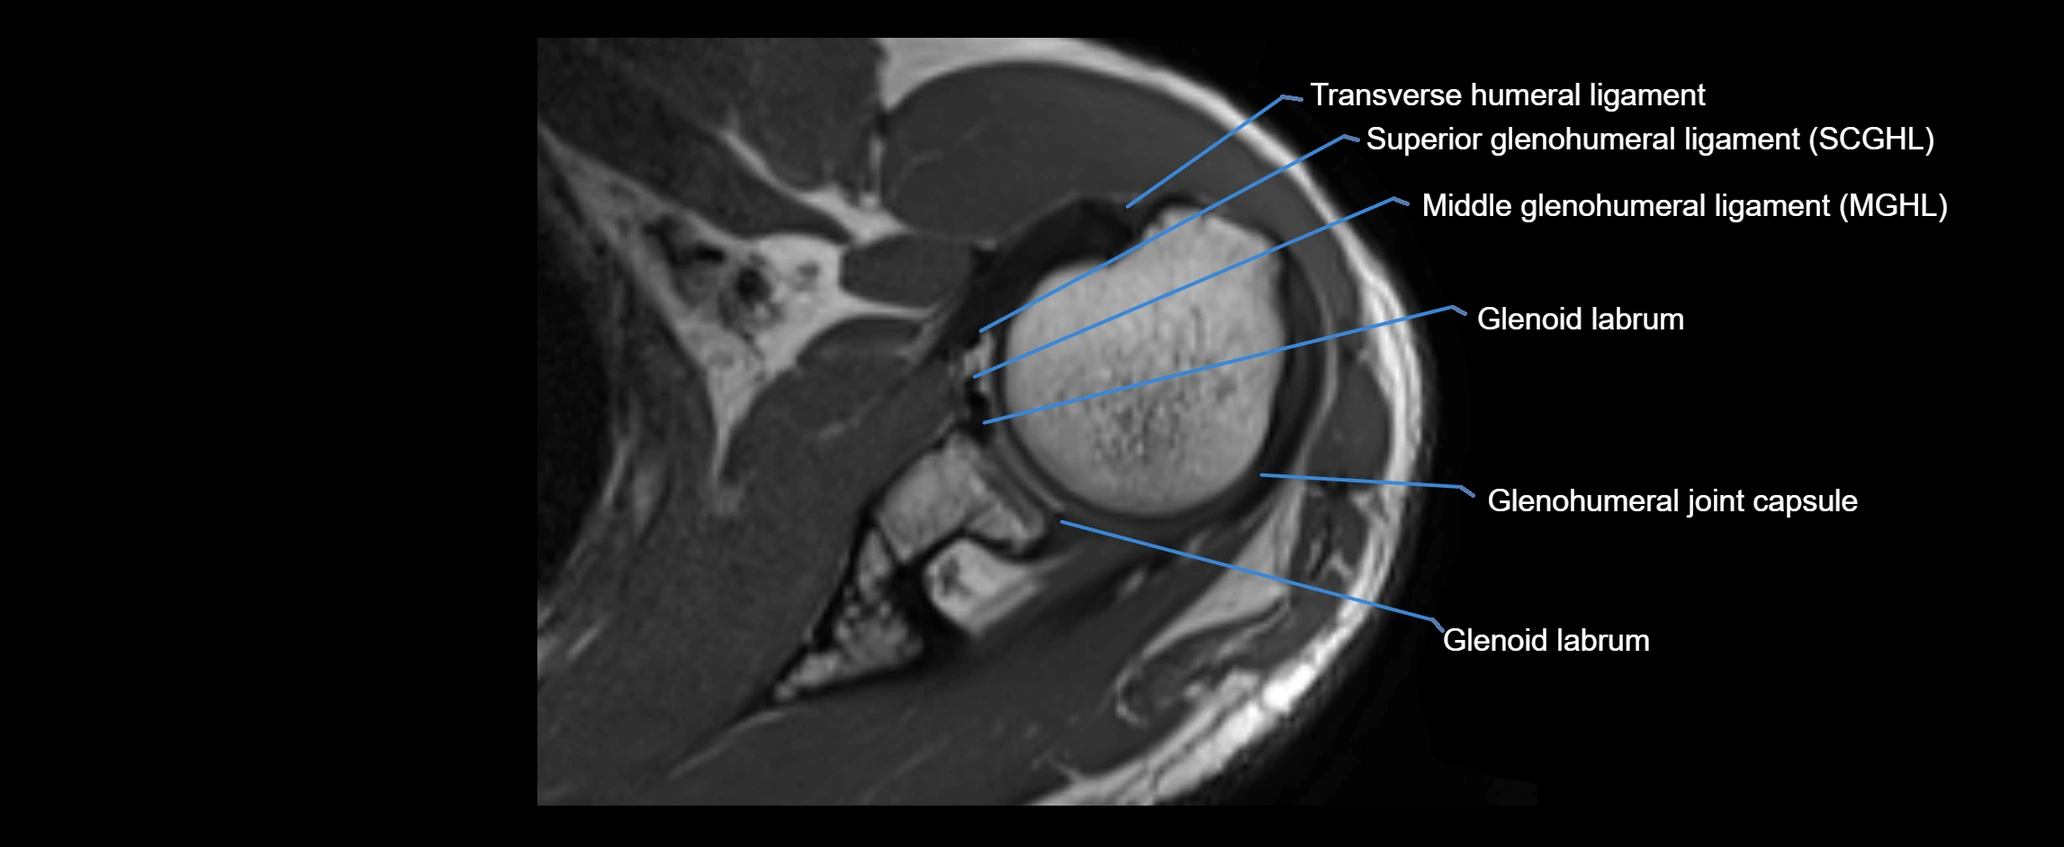

CT image

image